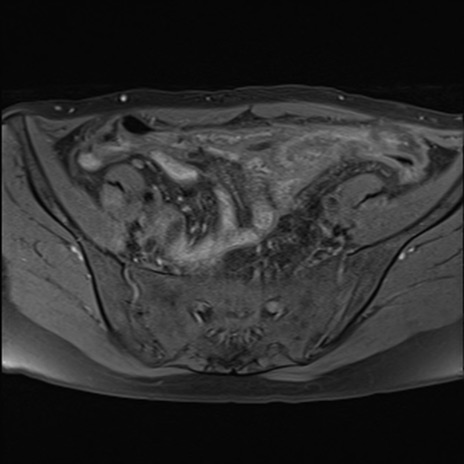

症例39 脂肪抑制T1WI(横断像)

MRI(4日後)

T1WI(横断像)